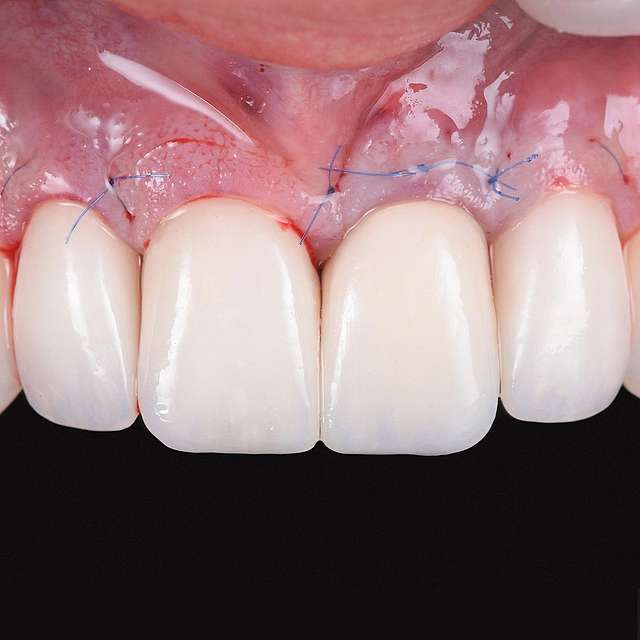

A gingival graft is a micro-surgery that will transplant a bulk of soft tissue - free gingiva or connective tissue ( the internal layer of gingiva ) to cover a soft tissue defect. Usually this type of procedures is required to augment implants, or to cover defects caused by periodontal disease or trauma. The grafts are harvested from the third molar region or the palate, and are transported where they are needed.

This type of procedure is a very delicate one, using the same type of blades like the ones used in ophthalmology and the sutures are also very thin. The sutures will be removed after 7-14 days, depending on the case, when primary healing is achieved. The maturation of the graft will take roughly 90 days, this is the reason why, when placing implants we prefer to also do the graft, so we can sync the healing time for both procedures.

Using tissue grafts to correct tissue defects

Using tissue grafts to correct gingival levels or cover recessions